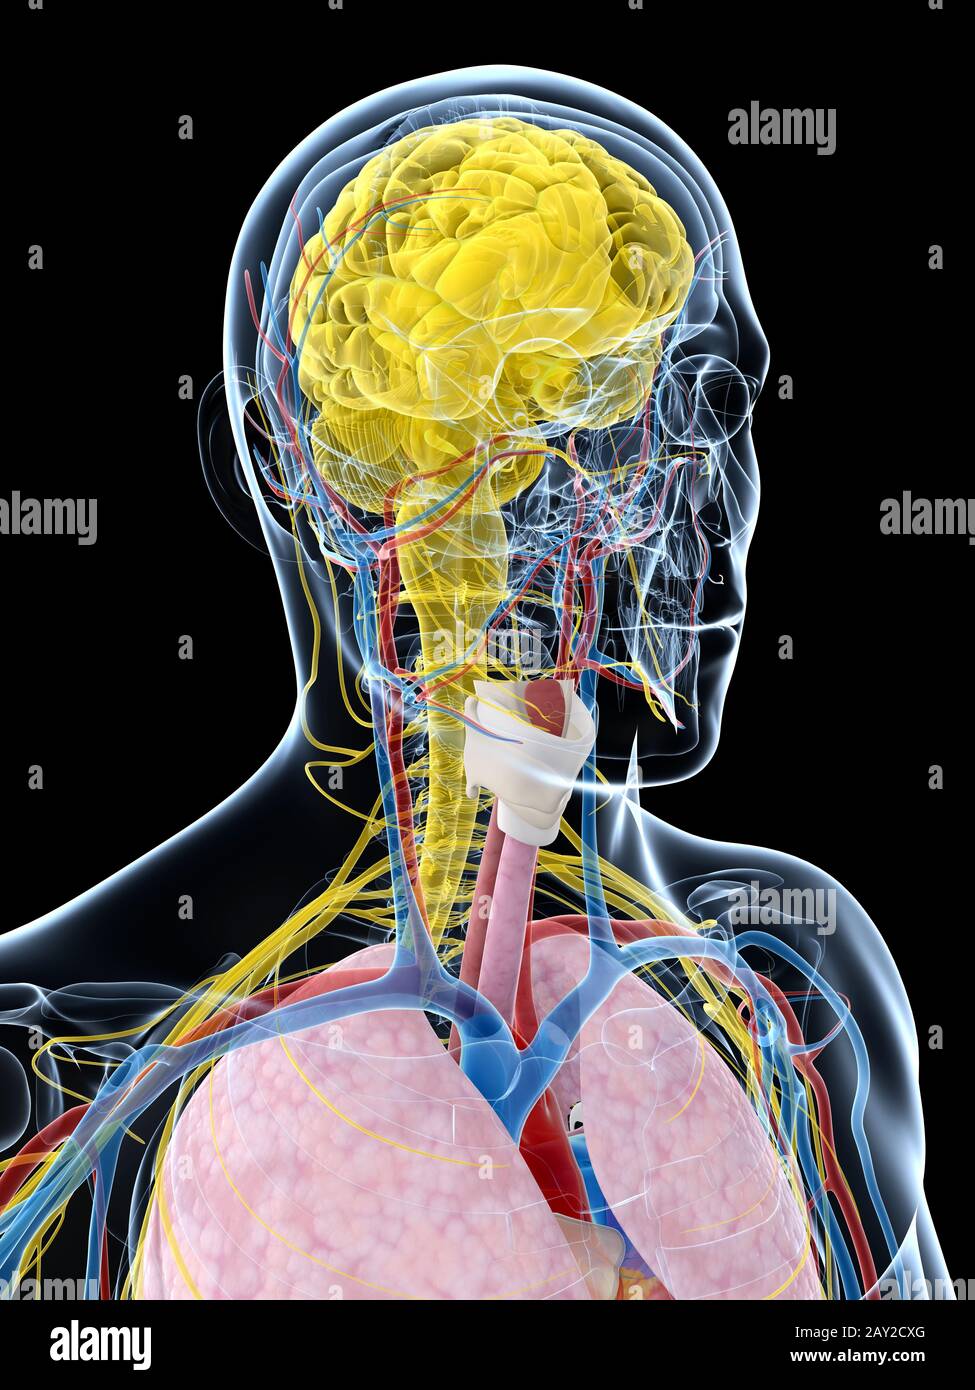

RF2N9P3NT–Röntgen des Schilddrüsenknorpels 3D-Darstellung mit männlichen Körperkonturen. Menschliche Anatomie, Medizin, Biologie, Wissenschaft, Gesundheitskonzepte.

RF2GB8D4J–3D-Darstellung des Verdauungssystems der männlichen Anatomie, zusammen mit anderen inneren Organen. Glasbild auf blauem Hintergrund, Vorderansicht.